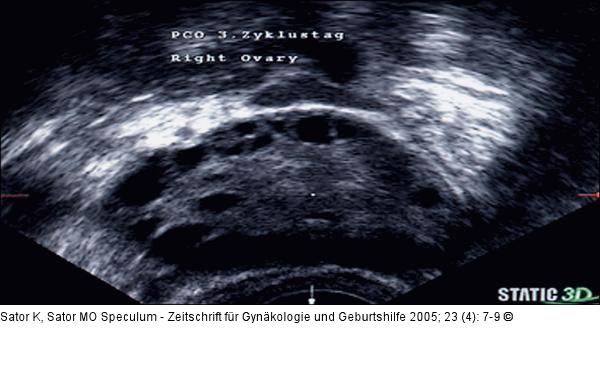

Abbildung 1: PCO Der sonographische Nachweis polyzystischer Ovarien ist für die Diagnosestellung des PCOS nach den Kriterien der National Health Konsensuskonferenz 1990 nicht erforderlich. |

Der sonographische Nachweis polyzystischer Ovarien ist für die Diagnosestellung des PCOS nach den Kriterien der National Health Konsensuskonferenz 1990 nicht erforderlich. |